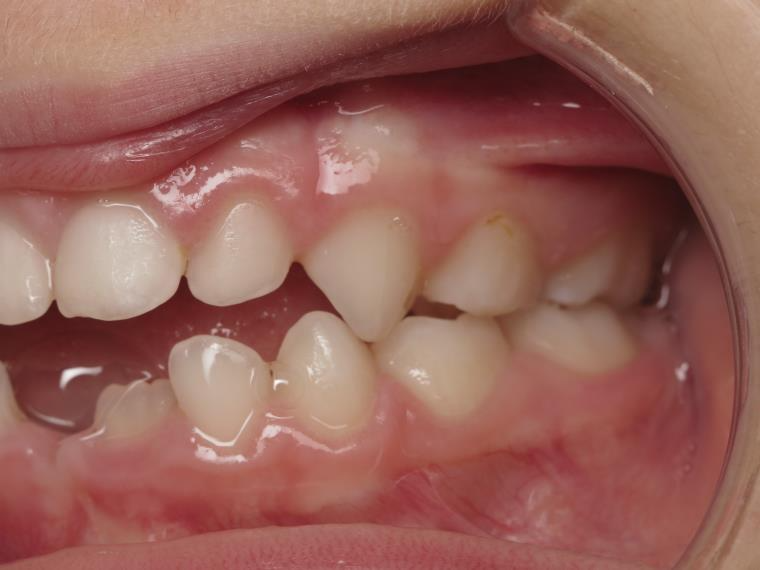

14 béance inversé gauche 5 ans

inversion postérieur coté droit et espace entre l'arcade du haut et du bas (béance)